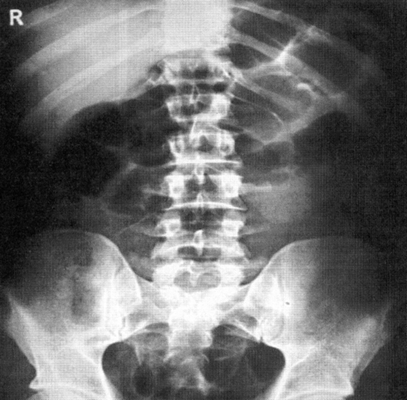

Рентгенография брюшной полости

Рентген активно используется для диагностики заболеваний органов брюшной полости. Широко распространена обзорная рентгенография брюшной полости - рентгенографическое исследование без введения контрастного вещества, позволяющая получить общую картину состояния брюшной полости.

Брюшная полость - это полость живота, которая ограничена сверху диафрагмой, спереди - брюшной стенкой, сзади - поясничной частью позвоночника, с боков - мышцами живота, снизу - подвздошными костями и диафрагмой таза. Внутри брюшной полости находятся органы пищеварительной системы - желудок, желчный пузырь, печень, кишечник, поджелудочная железа а также селезенка и органы мочевыделительной системы - почки и мочеточники.

Что показывает рентген брюшной полости?

Метод рентгендиагностики основан на том, что ткани различной плотности по-разному поглощают рентгеновские лучи. Более плотная, например, костная ткань хуже пропускает лучи, поэтому на снимке такая ткань оказывается светлее. Метод позволяет определить местоположение органов, их целостность, наличие инородных тел и новообразований.

Рентгенография брюшной полости показывает:

- как распределены газ и жидкость в брюшной полости, присутствует ли в брюшной полости свободная жидкость;

- присутствуют ли в брюшной полости инородные тела (проглоченные предметы в кишечнике, камни в желчном пузыре, камни в почках);

- имеются ли повреждения внутренних органов;

- имеет ли место внутрибрюшное кровотечение.

Рентген брюшной полости

С точки зрения оценки состояния конкретных органов обзорная рентгенография брюшной полости не очень информативна, однако она позволяет быстро определить, является ли картина патологической или нет. При разрыве стенки желудка или кишечника (прободение язвы или разрушении стенки опухолью) рентген покажет выходящий в свободную брюшную полость газ. С помощью рентгена брюшной полости можно диагностировать непроходимость кишечника и даже определить примерное место локализации проблемы.

Когда назначается рентген брюшной полости?

Обзорная рентгенография брюшной полости назначается при наличии жалоб на сильные боли в животе. Подобные боли могут наблюдаться при следующих заболеваниях:

- ; ; ;

- аппендицит;

- абсцессы и воспалительные заболевания органов брюшной полости;

- опухолевые процессы;

- ишемия кишечника; ;

- заворот кишечника.

Также обзорная рентгенография брюшной полости назначается при травмах живота.

Рентгенография брюшной полости . Обзорное исследование, которое проводится с контрастированием или без и позволяет уточнить диагноз при наличии жалоб пациента на сильные боли в животе.